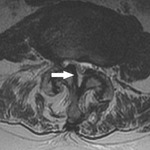

Axial view of a vertebral body showing central spinal stenosis

BMJ 2008;337:a2718; used with permission